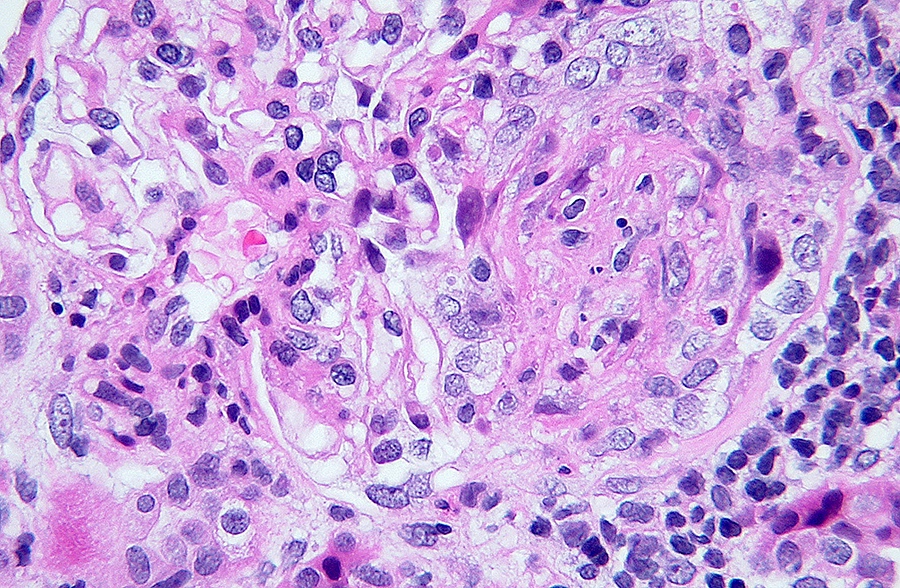

Microscopic (histologic) images

Contributed by Alexei Mikhailov, M.D., Ph.D.

- LN classes III - IV: lesions may be active (endocapillary or extracapillary proliferation) or chronic (sclerosing)

- Wire loop deposits, hyaline microthrombi, membranoproliferative lesions

- Fibrinoid necrosis and karyorrhexis may be present

- Crescent: a lesion consisting of extracapillary hypercellularity forming more than 2 cell layers, composed of a variable mixture of cells

- Fibrin and fibrous matrix may be present

- 10% or more of Bowman capsule should be involved (Kidney Int 2018;93:789)

- Cellular crescent: > 75% cells and fibrin and < 25% fibrous matrix (Kidney Int 2018;93:789)

- Fibrinoid necrosis: fibrin associated with glomerular basement membrane disruption or lysis of the mesangial matrix (Kidney Int 2018;93:789)

- Karyorrhexis: presence of apoptotic, pyknotic and fragmented nuclei (Kidney Int 2020;98:1120)

- Light microscopy: The biopsy consists of tissue from the renal cortex. The tissue is sampled at 10 levels of section with H&E, PAS, trichrome and PAMS stains. Per level of section up to 20 glomeruli are available, of which 2 are globally sclerosed and a few are segmentally sclerosed. 4 glomeruli display cellular crescents, fibrinoid necrosis and karyorrhexis in the capillary tuft and in the crescent. The nonsclerosed glomeruli display marked endocapillary hypercellularity. Tubules show focally flattened epithelium and absent brush borders; small foci of interstitial lymphocytic infiltration are seen. There is mild interstitial fibrosis and tubular atrophy. Arteries of the medium caliber are present and show mild intimal fibroelastosis; there is no significant arteriolar hyalinosis.